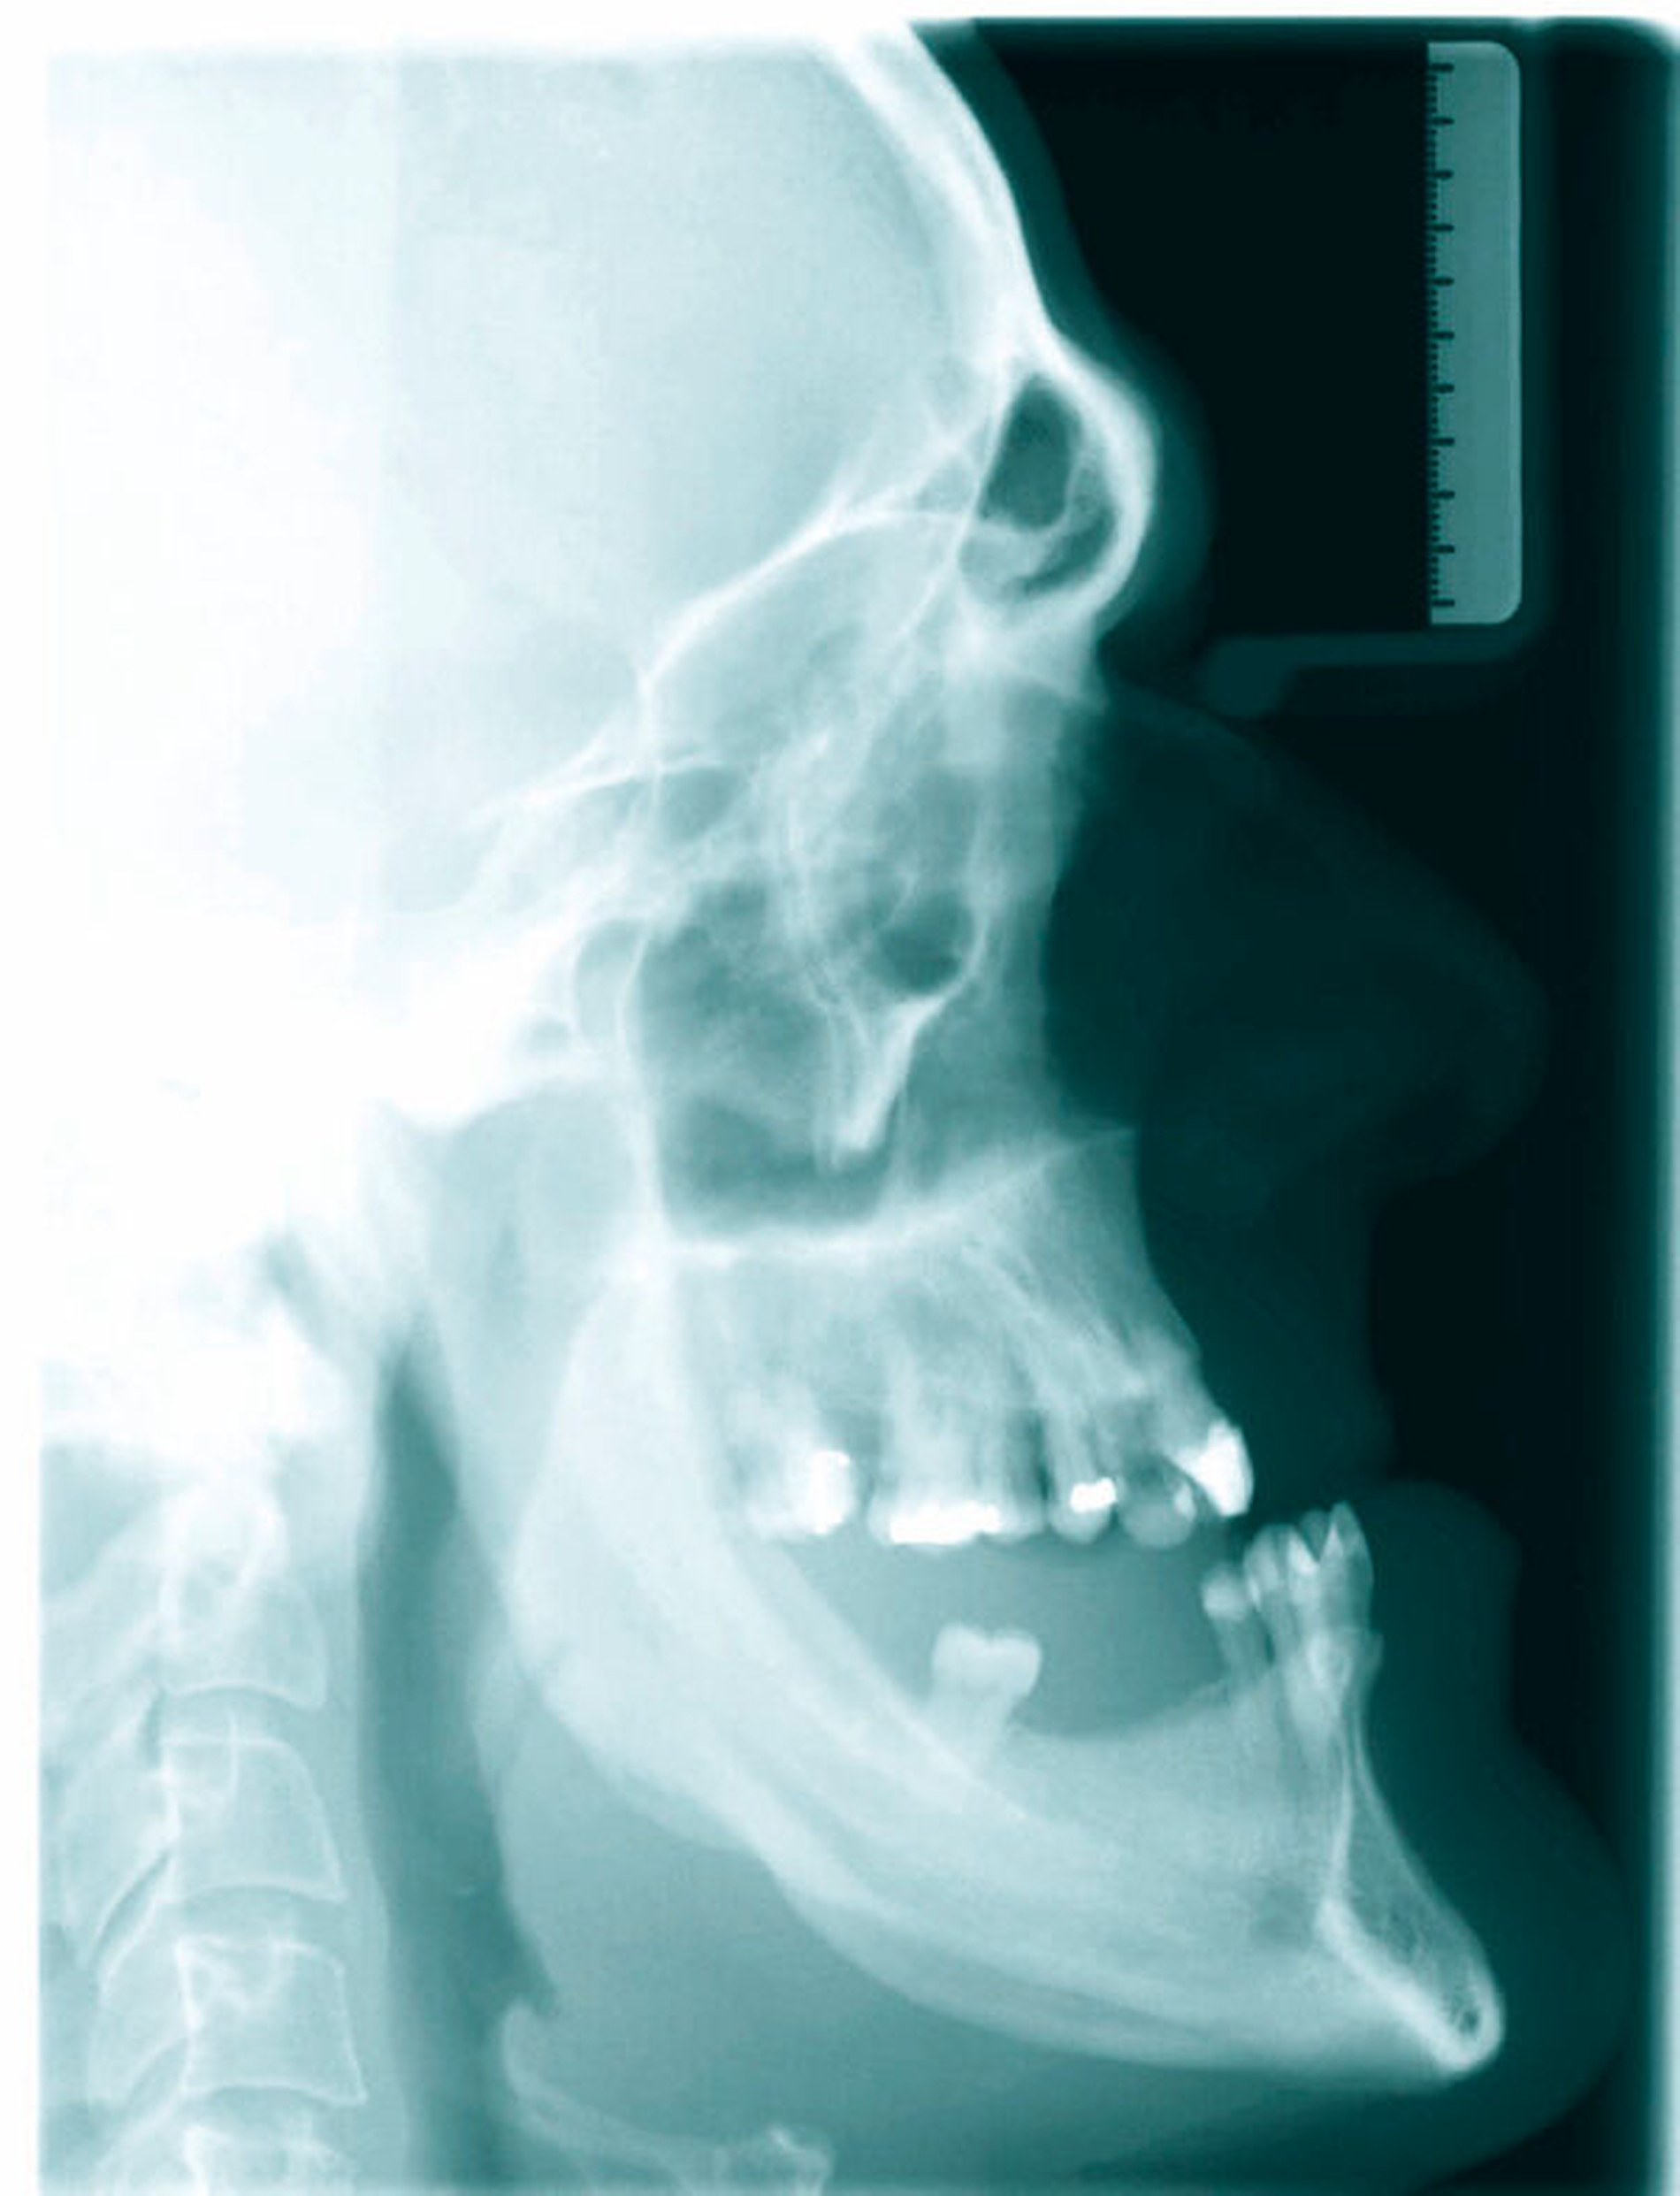

Der 39-jährige Patient (Abbildungen 1 und 2) suchte 2015 aufgrund einer zunehmenden Okklusionsstörung seinen Hauszahnarzt auf. Diesem fiel die ausgeprägte mandibuläre Hyperplasie auf und er überwies den Patienten zur endokrinologischen Diagnostik aufgrund des Verdachts auf eine Akromegalie. Im Rahmen der Anamnese äußerte der Patient zudem, dass er bereits vor einem Jahr eine Vergrößerung seiner Finger bemerkt habe.

Bei der ersten Vorstellung in der Dysgnathie-Sprechstunde imponierte eine 10 mm große, umgekehrte, sagittale Frontzahnstufe. Die Mittellinie des Unterkiefers wich um 4 mm nach rechts ab. Die Zähne des teilbezahnten Ober- und Unterkiefers hatten jeglichen Kontakt verloren (Abbildungen 5 und 7).

Die unverhältnismäßig große Zunge zeigte dentale Impressionen. Nach Festlegung des Zielbisses in Abstimmung mit den Kollegen der Prothetik erfolgte eine bimaxilläre Umstellungsosteotomie mit Vorverlagerung des Oberkiefers um 8 mm nach LeFort-I-Osteotomie und Rückverlagerung des Unterkiefers nach sagittaler retromolarer Osteotomie (Abbildungen 6 und 8). Im gleichen Zug wurde eine Zungenreduktionsplastik nach Rheinwald [Egyedi et al., 1964] durchgeführt.